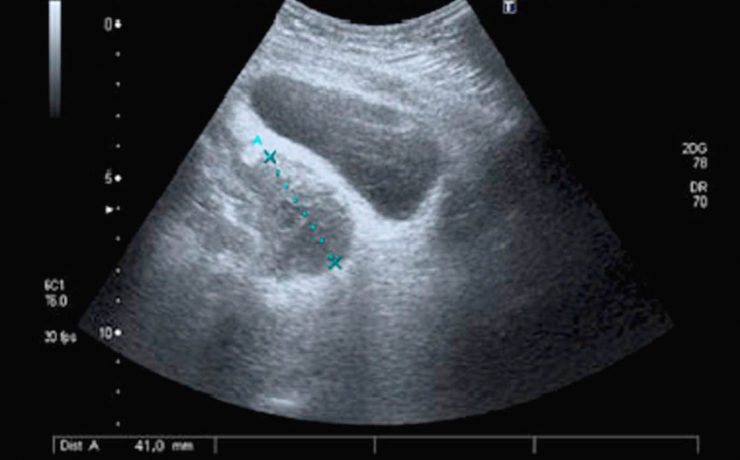

La vesícula biliar se divide en fundus, cuerpo y cuello, en el cuello puede haber un infundíbulo o “Bolsa de Hartmann” Puede haber falta de visualización por: Colecistectomía previa Contracción fisiológica Conducto de vesícula biliar fibrosado: colecistitis crónica Vesícula biliar llena de aire o colecistitis enfisematosa Agenesia Localización ectópica PATOLOGIA